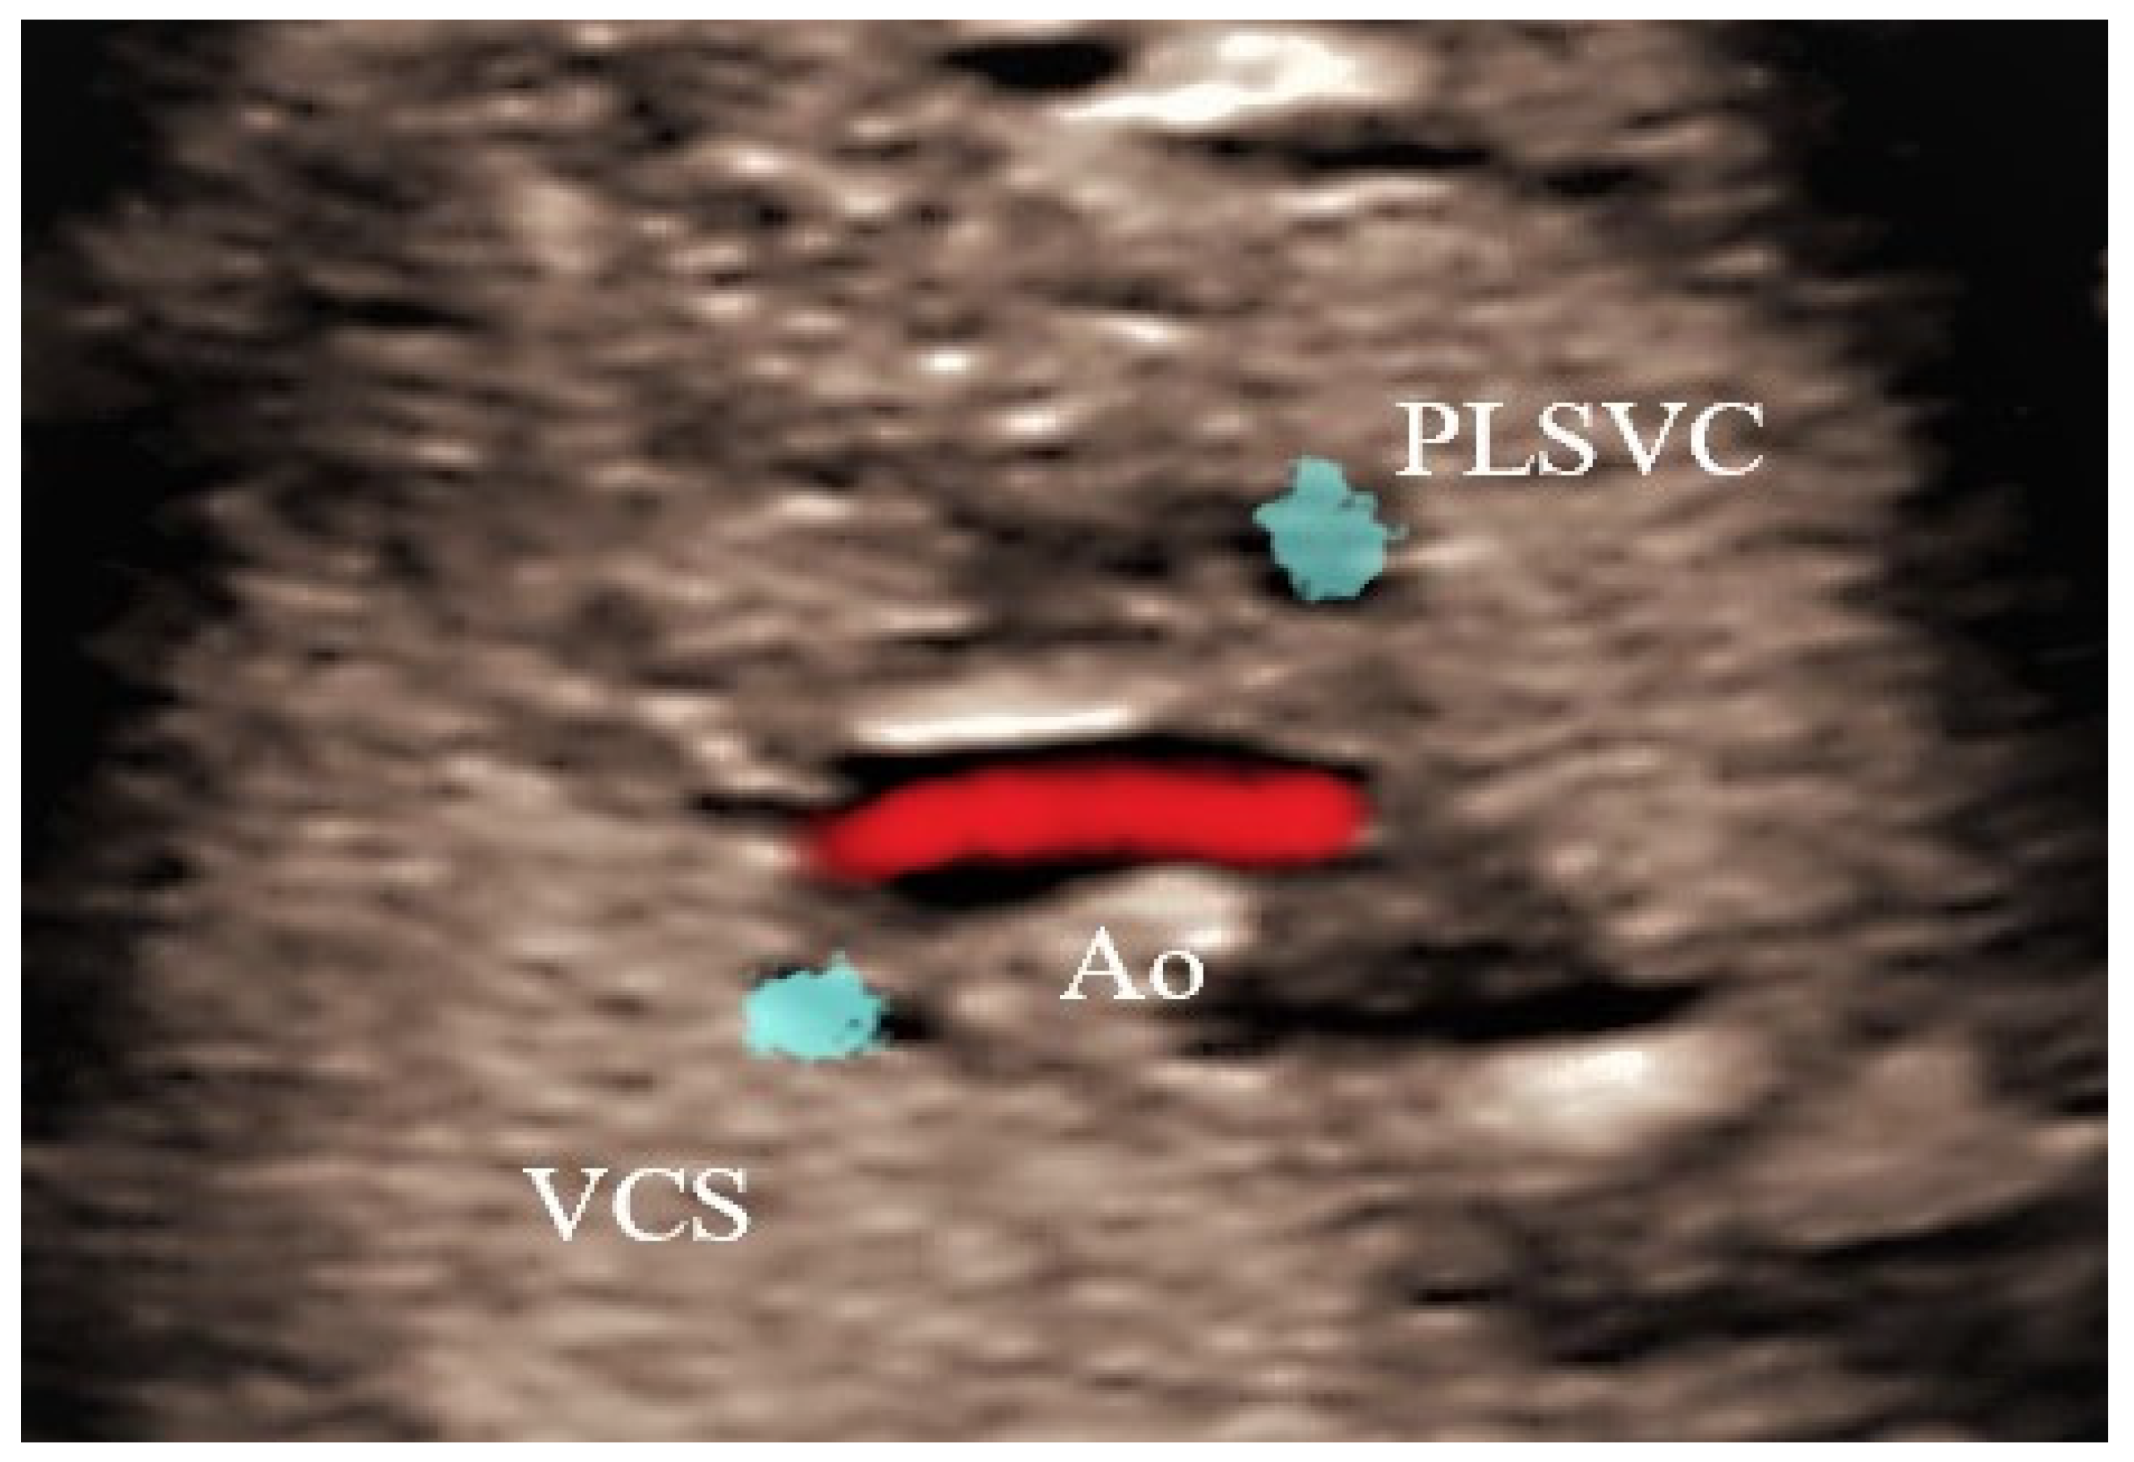

4.4. Case 4